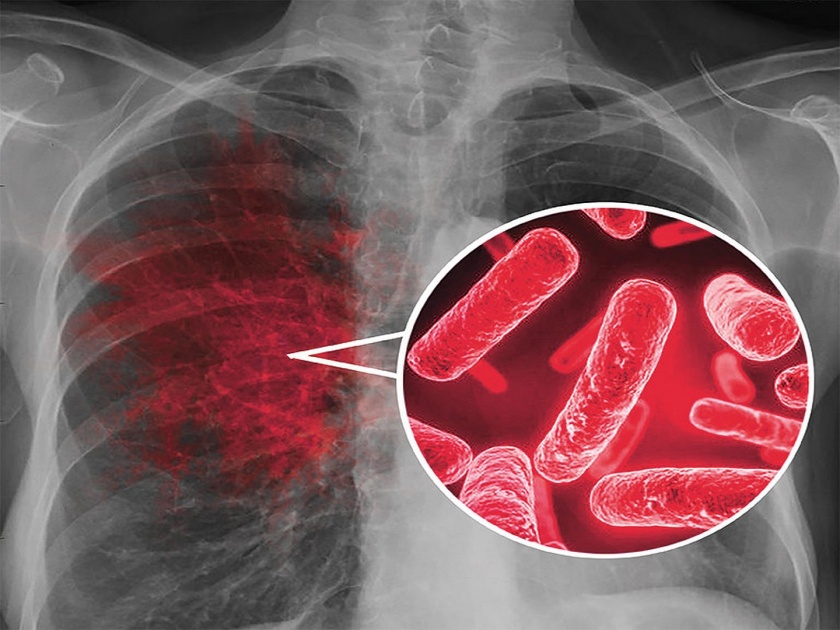

Immunologic Tuberculosis म्हणजेच टीबीशी संबंधित नुकताच करण्यात आलेला एक रिसर्च समोर आला आहे.

Immunologic Tuberculosis म्हणजेच टीबीशी संबंधित नुकताच करण्यात आलेला एक रिसर्च समोर आला आहे. या रिसर्चनुसार अनेक केसेसमध्ये टीबीशी संबंधित स्किन आणि ब्लड टेस्ट पॉझिटीव्ह आल्यावरही प्रभावित व्यक्तीला टीबी हा आजार होत नाही. अभ्यासकांनुसार, याचं कारण म्हणजे त्या व्यक्तीचं स्ट्रॉंग इम्यून सिस्टीम असतं.

sciencedaily.com ने दिलेल्या वृत्तानुसार, या रिसर्चचे अभ्यासक पुढे सांगतात की, स्टॉंग इम्यून सिस्टीम म्हणजेच मजबूत रोगप्रतिकारक शक्तीमुळे ब्लड आणि स्किन टेस्ट टीबी पॉझिटीव्ह आल्यावरही काही लोकांना टीबी होत नाही. कारण त्यांच्या शरीरात हा आजार डेव्हलपच होऊ शकत नाही. असं इन्फेक्शन ऑर्गेनिजमच्या कारणाने होतं. याद्वारे मायक्रोबॅक्टेरियम टर्ब्यूक्लॉसिसला इम्यून सिस्टम द्वारे नैसर्गिक पद्धतीने नष्ट करून शरीराच्या बाहेर केलं जातं. अशात हा आजार वाढत नाही.